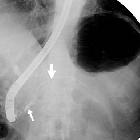

ERCP

Endoscopic pancreatography shows active extravasation of contrast injected into the main pancreatic duct .